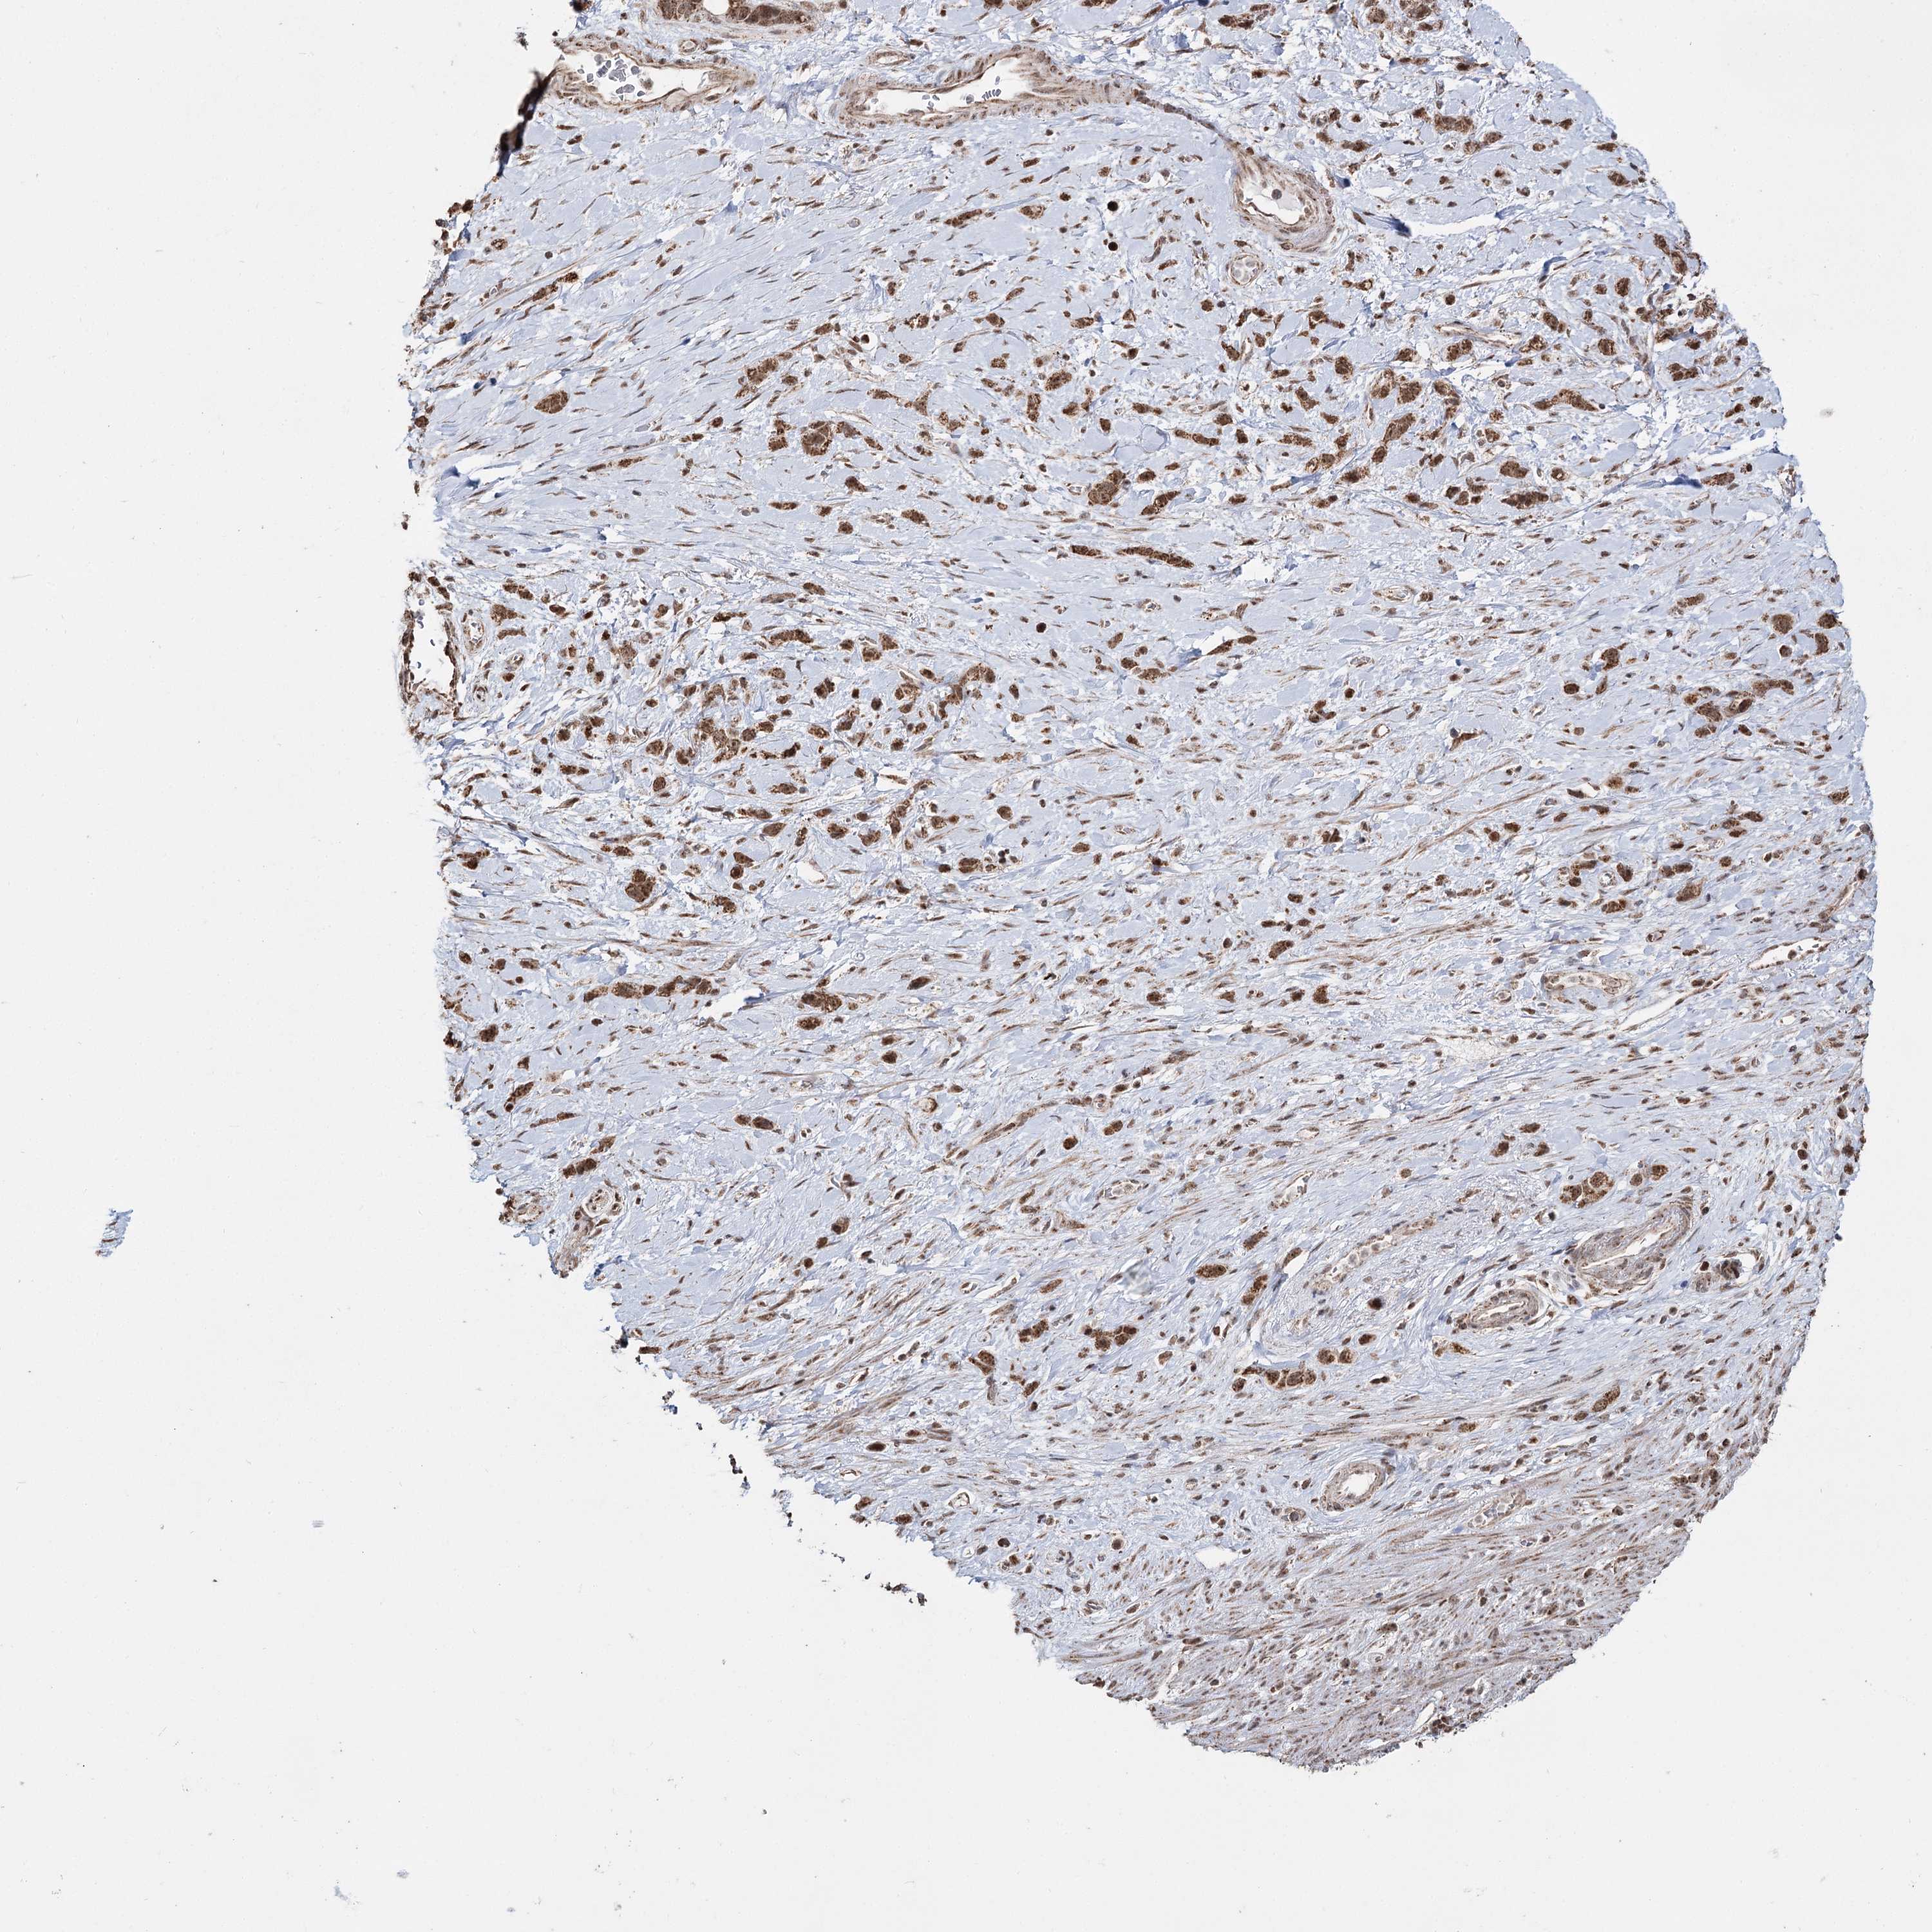

STOMACH CANCER - Protein expressioni

A mouse-over function shows sample information and annotation data. Click on an image to view it in a full screen mode. Samples can be filtered based on level of antibody staining by selecting one or several of the following categories: high, medium, low and not detected. The assay and annotation is described here.

Note that samples used for immunohistochemistry by the Human Protein Atlas do not correspond to samples in the TCGA dataset.

Antibody stainingi

Antibody staining in the annotated cell types in the current human tissue is reported as not detected, low, medium, or high, based on conventional immunohistochemistry profiling in selected tissues. This score is based on the combination of the staining intensity and fraction of stained cells.

Each image is clickable and will lead to virtual microscopy that enables deeper exploration of all samples and also displays staining intensity scores, fraction scores and subcellular localization as well as patient and tissue information for each sample.

Antibody HPA038484

Antibody HPA038485

Staining

High

Medium

Low

Not detected

Intensity

Strong

Moderate

Weak

Negative

Quantity

>75%

75%-25%

<25%

None

Location

Nuclear

Cytoplasmic/membranous

Cytoplasmic/membranous,nuclear

Adenocarcinoma, NOS

Adenocarcinoma, High grade